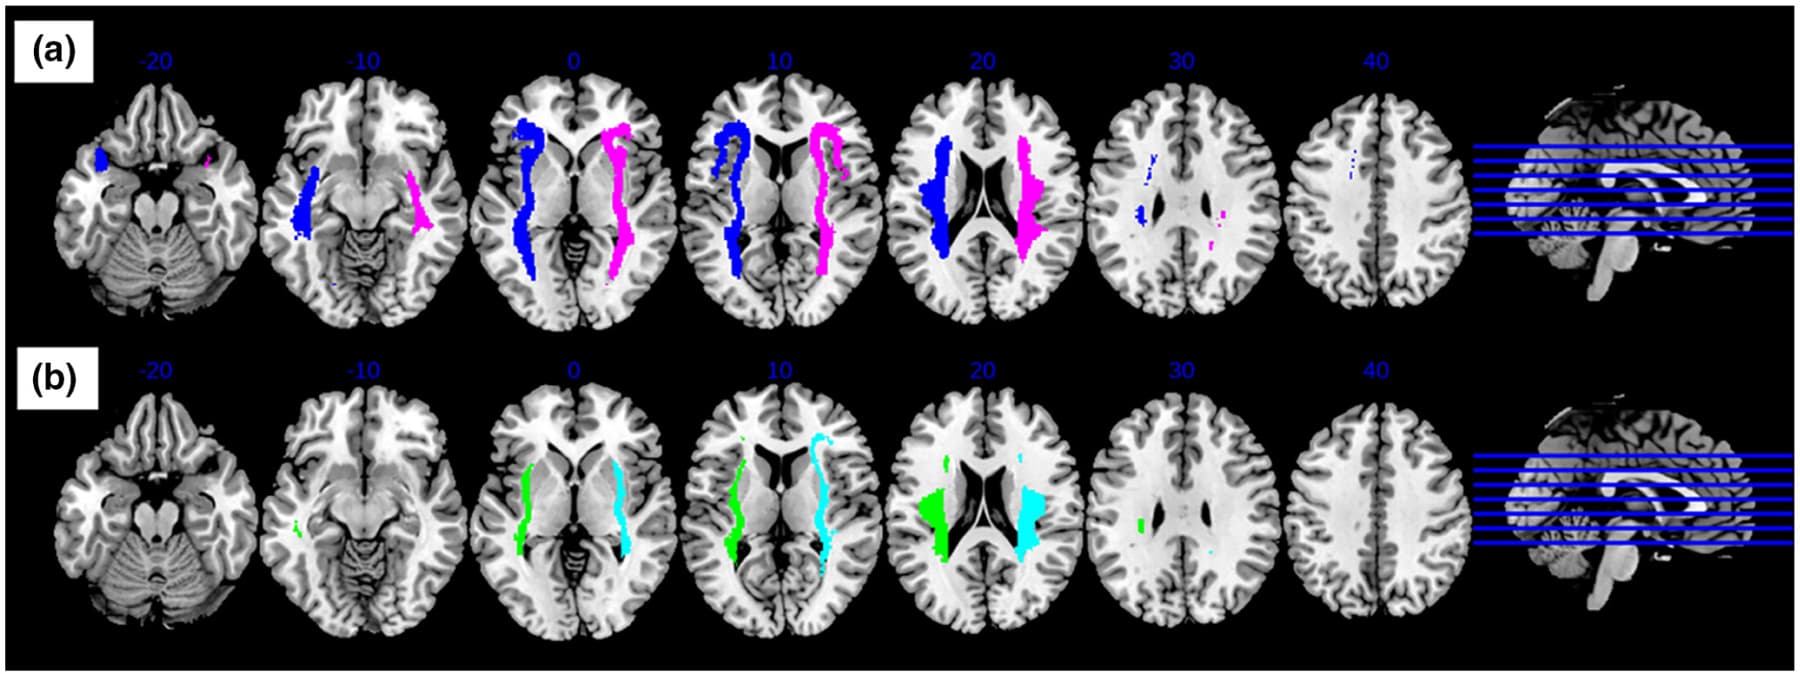

First, the probabilistic tractography was generated between each insula ROI and the rest of the brain, for all subjects using AFNI software (FA threshold = 0.2, tracts per voxel threshold = 0.001, number of seeds per voxel per iteration = 5, number of Monte Carlo iterations = 1000). Afterwards, the probabilistic tractography for each subject was binarized and summed before thresholding at 25% to create a map. The map consisted of connecting fiber tracks present in at least 25% of all the subjects, in order to ensure that the map represented tractography of both AUD and healthy individuals. Group maps representing the WM connectivity between each of the insula ROIs and the rest of the brain were created (Figure 2).

Group probabilistic maps created for the anterior insula revealed connectivity involving the inferior frontal, anterior temporal, and inferior parietal regions. The maps created for the posterior insula revealed connections involving the anterior temporal and inferior parietal regions.

The connectivity analysis showed significant differences between groups (control > AUD) for only the left and right anterior insula (pFWE < .025, Table 3), where connectivity was higher in the control group. The clusters that significantly differed in FA of the left anterior insula tractography between healthy controls and AUD groups belonged to the left inferior fronto-occipital fasciculus (IFOF), and left uncinate fasciculus. For the right anterior insula, the clusters belonged to the forceps major and right inferior fronto-occipital fasciculus. There were no structural connectivity differences observed in either left or right posterior insula between healthy controls and AUD groups. Connectivity analysis performed using the MD images complemented the FA results reported above. Results from this analysis can be found in the supplement.

Overall, we found significantly greater resting state connectivity for both the anterior and posterior insula with frontal, parietal, temporal, and occipital regions in controls compared to AUD (p < .025, FDR corrected, a cluster size of k > 120 determined using 3dClustSim, Figures 3 and 4).

Specifically, significantly higher connectivity was observed between the left anterior insula and the left occipital cortex, middle cingulate gyrus, right cerebellum, left superior temporal gyrus, and left precuneus (Figure 3a), while higher right anterior insula connectivity was observed with the left and right cuneus, as well as the left superior temporal gyrus (Figure 3b). Connectivity between the left anterior insula and the right cerebellum is potentially even lower in AUD participants that also smoked (Table S1).

For the left posterior insula, higher connectivity was observed with the left cuneus, left superior temporal gyrus, left precuneus, right middle cingulate gyrus, and right cerebellum (Figure 4a). Very similarly, for the right posterior insula, increased connectivity was observed with the same regions (except the left precuneus) as the left posterior insula (Figure 4b).